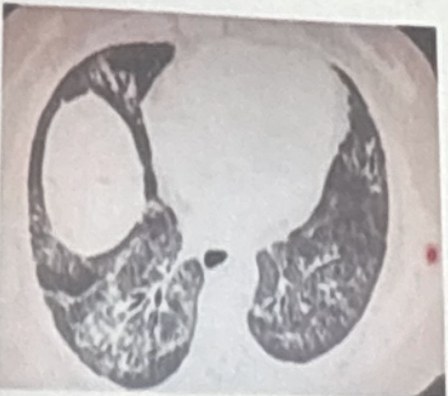

¿Qué patrón tomográfico corresponde a NINE?

A

• vidrio despulido

• patron reticular

• predominio peribroncovascular

¿Qué patrón tomográfico corresponde a neumonitis por hipersensibilidad?

Vidrio despulido + nódulos centrolobulillares.

¿Cuáles son patrones de aumento de atenuación en TAC?

• Reticular

• Consolidación

• Nódulos

• Atelectasia

• Crazy paving